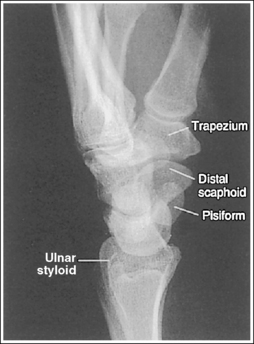

The wrist has been externally rotated to a 45-degree PA oblique projection. The trapezoid and trapezium are demonstrated without superimposition, and the trapeziotrapezoidal joint space is open. The scaphoid tuberosity and waist are demonstrated in profile. Only a small degree of trapezoid and capitate superimposition is present.

• To accomplish a PA oblique wrist projection, begin with the wrist in a PA projection, with the humerus and the forearm on the same horizontal plane. Externally rotate the hand and wrist until the wrist forms a 45-degree angle with the IR (Figure 4-35). When judging the degree of wrist obliquity, it is best to view the wrist and not the hand. The obliquity of the hand and wrist are not always equal when they are rotated, especially if the humerus and forearm are not positioned on the same horizontal plane for the image.

• Determining the accuracy of wrist obliquity. On a PA wrist projection (see Image 39), the trapezoid and trapezium are superimposed. Placing the wrist in a 45-degree externally rotated PA oblique projection draws the trapezium from beneath the trapezoid, providing clear visualization of both carpal bones and the joint space (trapeziotrapezoidal) between them. The PA oblique projection also rotates the scaphoid tuberosity and waist into profile. The relationships between the trapezoid and trapezium and the trapezoid and capitate are used to discern an accurate PA oblique wrist projection. If the wrist is underrotated, the trapezoid and trapezium are superimposed, the trapeziotrapezoidal joint space is obscured, and the trapezoid demonstrates minimal capitate superimposition (see Image 40). If wrist obliquity is more than 45 degrees, the trapezium demonstrates minimal trapezoidal superimposition, the capitate is superimposed by the trapezoid, and the trapeziotrapezoidal joint space is obscured (see Image 41).

The second CM and the scaphotrapezoidal joint spaces are demonstrated.

The long axes of the third metacarpal and midforearm are aligned with the long axis of the collimated field. The scaphoid tuberosity and waist are demonstrated in profile and are not positioned directly next to the radius.

The ulnar styloid is in profile at the far medial edge.